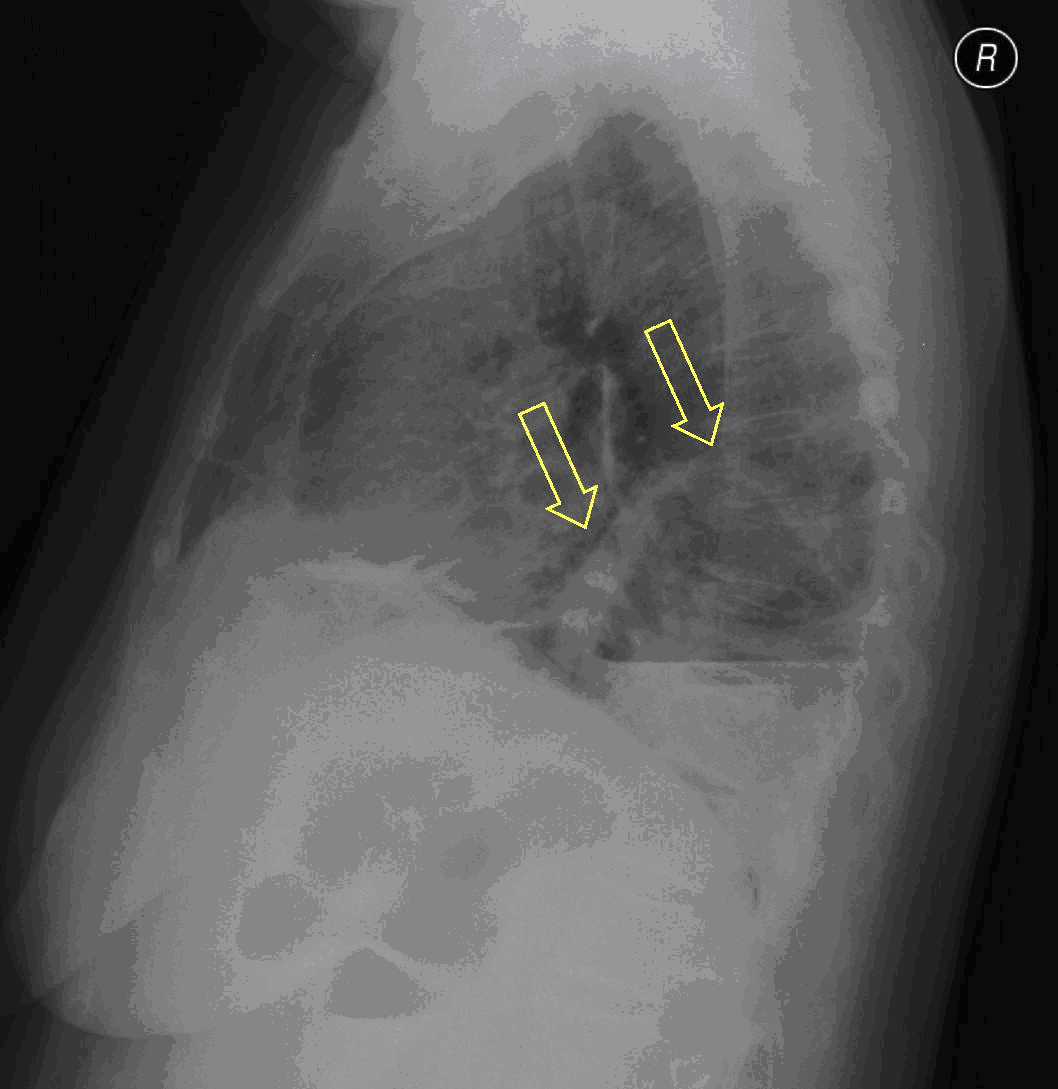

23. Pulmonary metastases, bidirectional (PA and right lateral) plain chest radiograph.

51 year old woman, endometrial carcinoma. Numerous ring shadows bilaterally in basal dominance (max. appr. 12 mm). Left pleural effusion of one finger wide.